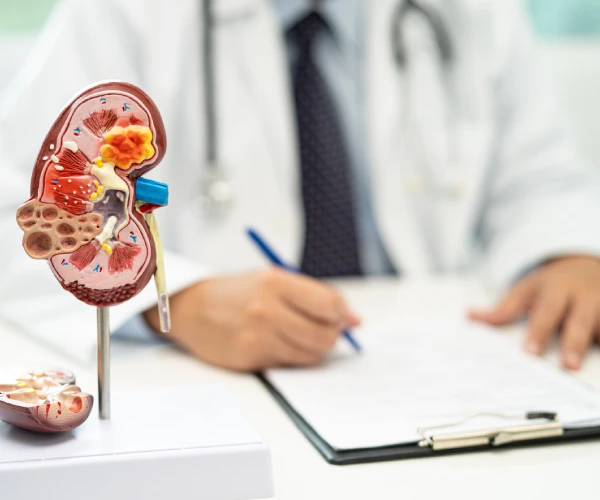

Dr. Andrés Horacio Ortiz

Experiencia Médica:

Más de 10 años de trayectoria en diagnóstico y tratamiento de enfermedades renales, respaldado por certificación del Consejo Mexicano de Nefrología.

Atención Integral:

Evaluación completa, interpretación de estudios clínicos y acompañamiento médico continuo, con enfoque humano y profesional.

Tecnología y Precisión:

Uso de equipos modernos y técnicas especializadas que permiten obtener resultados confiables y un diagnóstico temprano de alteraciones renales.

Dr. Andrés Horacio Ortiz

Especialista en Consulta Nefrológica

Certificado por el Consejo Mexicano de Nefrología

Confianza y Experiencia en Nefrología